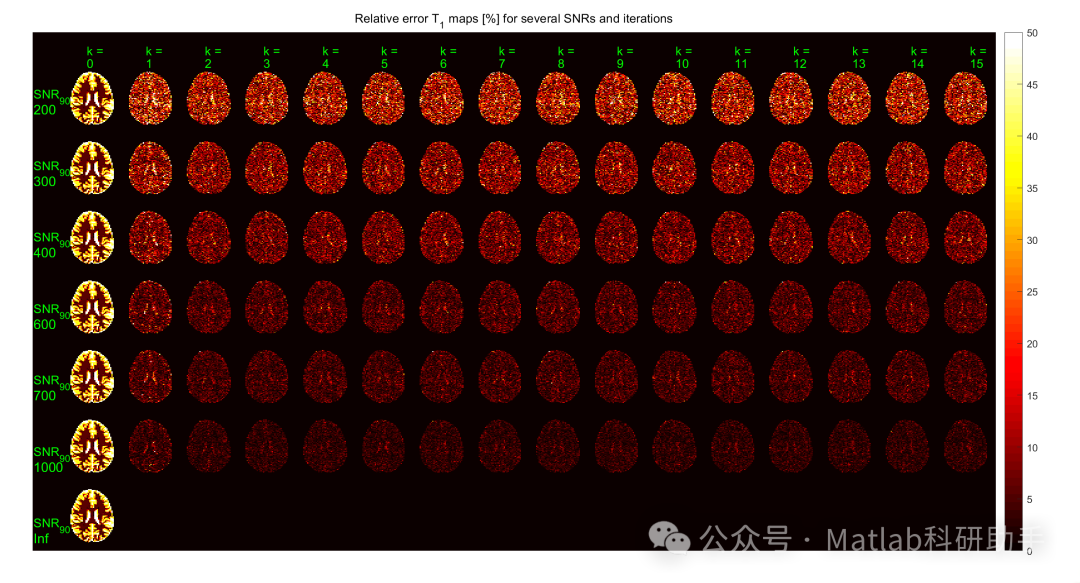

⛳️ 运行结果